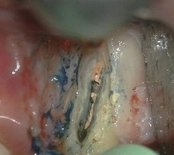

Upper molar failed root canal and apicoectomy:

Before

Immediately after

3-month follow-upThis person presented with one root that had failed from root canal treatment. The arrow in the picture, shows the infection as well as extra filling material that was pushed out of the root. An apical microsurgery was performed using the laser. The infection and excess material was cleaned out. Complete healing is visible 3 months after. The tooth was saved. This is a poor area for an implant.